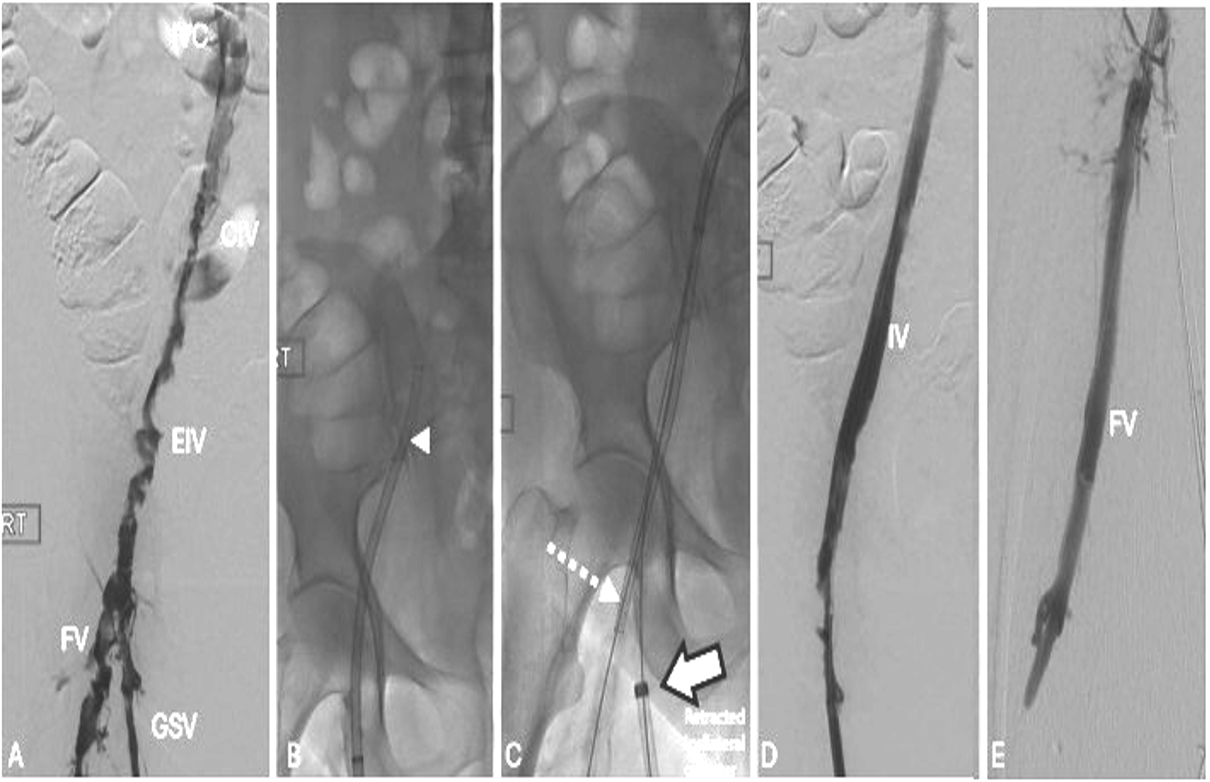

使用左侧大隐静脉(GSV)和对侧右股骨静脉(CFV)的左下肢体血栓切除术的双访问技术(CFV)。

A:静脉造影显示下腔静脉(IVC)、左髂总静脉(CIV)和髂外静脉(EIV)血栓形成。由于阻塞,下腔静脉和近端髂总静脉未显影。对侧入路临时栓塞保护(箭头)。B:从大隐静脉入路使用“闪电闪光”进行髂静脉顺行血栓切除术,显示了梅-瑟纳综合征压迫点(虚线箭头)。C:从大隐静脉入路置入支架。D:从对侧髂总静脉入路使用“闪电闪光”进行股深静脉(PFV)、股静脉(FV)和腘静脉(未显示)的上行-下行逆行血栓切除术,同时将大隐静脉鞘管回撤。最终静脉造影显示流入静脉通畅。